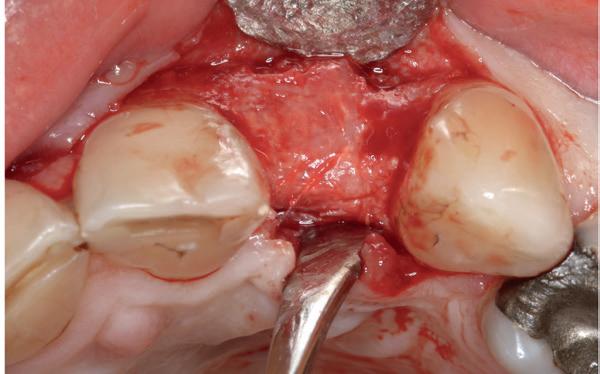

Voor de aanvulling zachte weefsels chirurgie werd gekozen voor de VISTA techniek, hierbij worden er twee incisies partial thickness flap hoog in de mucosa gemaakt, waarna er ruimte vanuit de incisies wordt getunneld tussen de gingiva en het periost door middel van VISTA tunnel instrumenten. Uit het palatum links werd een vrij gingivatransplantaat geoogst van 15x10 mm met een dikte van 3 mm, die voor inhechten werd geëpithelialiseerd. Als het epitheel niet wordt verwijderd, kan deze graft door

de mucosa heen groeien, dat ten koste gaat van de esthetiek. In het donorgebied wordt een collageen spons ingehecht, waardoor de patiënt daar minder last van heeft. Het bindweefsel wordt door de hul-

pincisies met hechtingen naar het buccale en coronale deel getrokken en aldaar ingehecht. Met twee incisies werd ook de emergence profile gecreëerd (afbeelding 6-13). Voor een goede genezing van het

5. Beginsituatie voor behandeling

6. VISTA techniek twee hulp incisies

7. Vervaardiging tunnel met tunnelinstrumenten

8. Geoogst bindweefseltransplantaat uit palatum

9. Na de-epithelialiseren van transplantaat

10. Inhechten van een collageenspons in het donorgebied

11. Middels hechtingen het op de juiste plek trekken van het transplantaat

12. Transplantaat ingehecht

13. Occlusaal beeld verdikking van de zachte weefsels